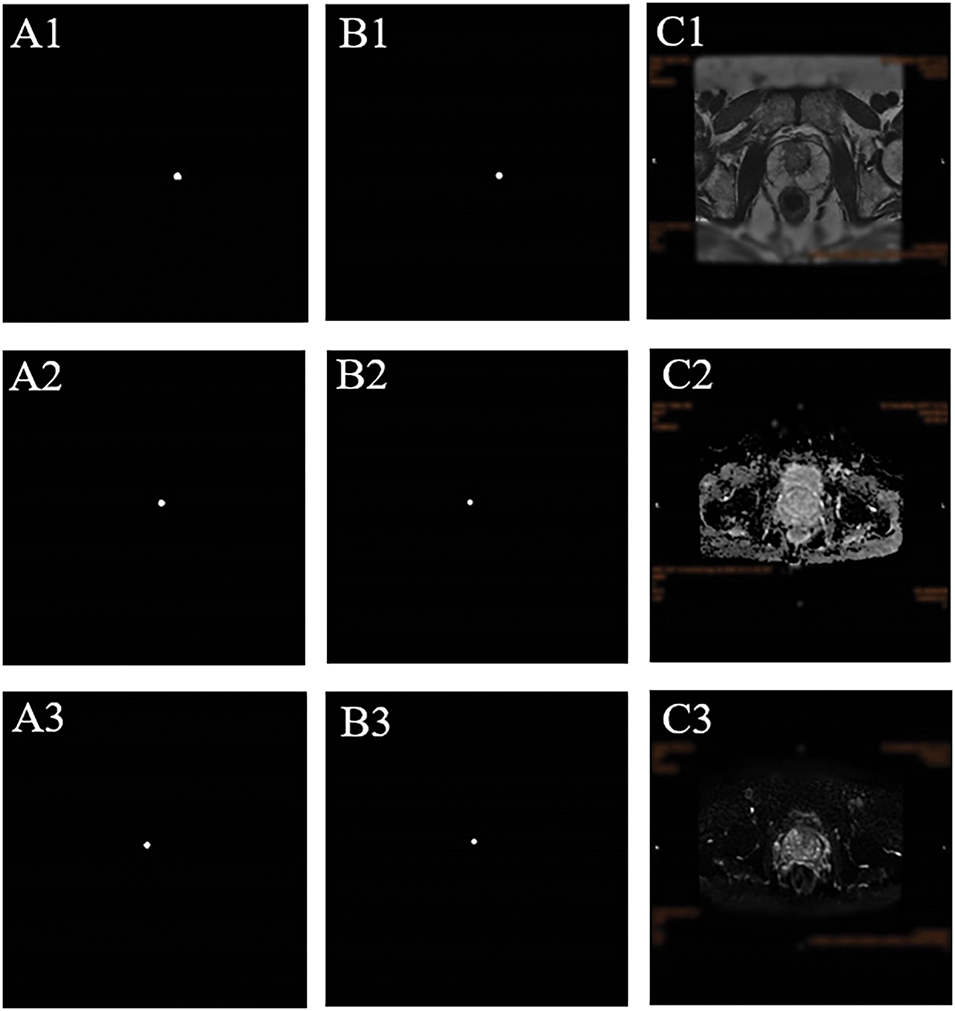

Each histopathological specimen included in this study has been re-read by another full-experienced pathologist, and the pathologically confirmed tumor puncture sites were located on the MR images (Figure 2). Among the 150 patients, 9 (6%) underwent repeat transperineal biopsy during follow-up.

FIGURE 2. The position of prostate cancer in MRI was determined according to pathological findings. (A1–3) Pathological images of prostate cancer (10×). (B1–3) 40×. (C) The white arrow indicates the location of the prostate cancer in the MRI pictures (C1: T2 weighted imaging [T2WI]; C2: diffusion-weighted imaging, [DWI]; C3: apparent diffusion coefficient, [ADC])